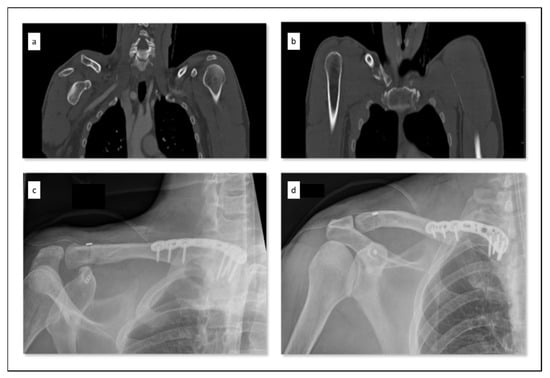

Figure 7.

Example of recommended treatment strategy for a clavicular combination injury (CCI) type IIa in the case of bipolar injury to the shoulder girdle. A male patient with 45 years of age was injured because of a bicycle accident. The computed tomography showed a combination of an acromioclavicular joint dislocation (a) and an ipsilateral medial clavicle fracture (b). This CCI was surgically treated with open reduction and internal plate fixation of the medial clavicle (Variax, Stryker) and acromioclavicular joint reconstruction (Tightrope, Arthrex) in one session (c,d).